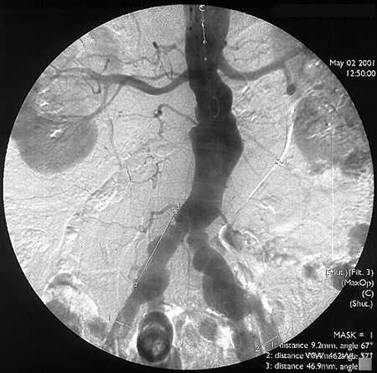

Ocluzia arterei iliace primitive drepte si stenoza arterei iliace primitive

stangi

Arteriografie.

Colaterale bogate (hipertrofie de artere lombare).

Reinjectarea portiunii distale a arterei iliace primitive drepte in amonte de

bifurcata iliacei.